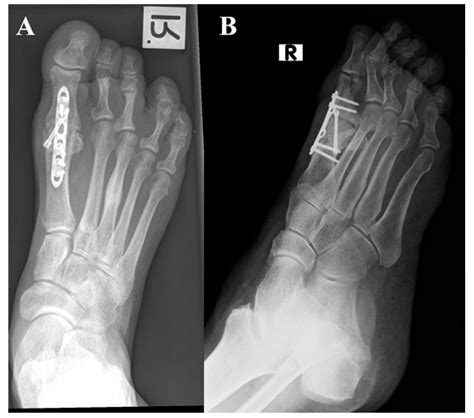

When conservative treatments fail to provide relief, surgical intervention may be necessary. The type of surgery depends on the specific condition and the extent of the damage. Common surgical procedures for 1st MTP joint issues include:

• Cheilectomy: This procedure involves removing bone spurs or other obstructions that limit joint movement.

• Osteotomy: Realigning the bones to correct deformities and improve joint function.

• Arthrodesis: Fusing the joint to eliminate pain and improve stability, although this limits mobility.

• Arthroplasty: Replacing the damaged joint with an artificial implant to restore function and reduce pain.